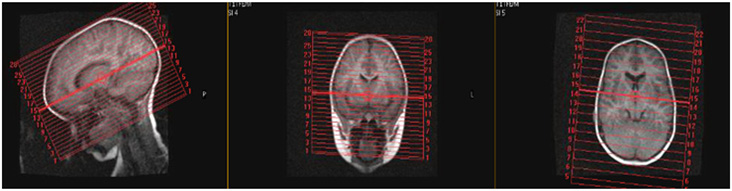

| AXIAL | T2 | SS TSE | 3 | 0 | no | 20-22 | no | Angle to Corpus- Skull Base to Vertex |

| SAG | T2 | SS TSE | 4-5 | 1 | no | 20-22 | no | Scalp to Scalp |

| COR | T2 | SS TSE | 4-5 | 1 | no | 20-22 | no | Angle to Corpus- Skull Base to Vertex |